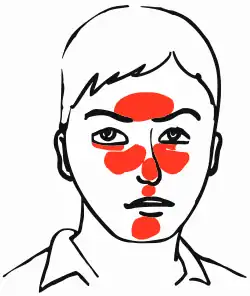

| Rosacea over the cheeks and nose[1] | |

Rosacea is a long-term skin condition that typically affects the face.[2][3] It results in redness, pimples, swelling, and small and superficial dilated blood vessels.[2] Often, the nose, cheeks, forehead, and chin are most involved.[3] A red, enlarged nose may occur in severe disease, a condition known as rhinophyma.[3]

Rosacea typically begins with reddening (flushing) of the skin in symmetrical patches near the center of the face.[11] Common signs can depend on age and sex: flushing and red swollen patches are common in the young, small and visible dilated blood vessels in older individuals, and swelling of the nose is common in men.[11] Other signs include lumps on the skin (papules or pustules) and swelling of the face.[11] Many people experience stinging or burning pain, and rarely itching.[11]